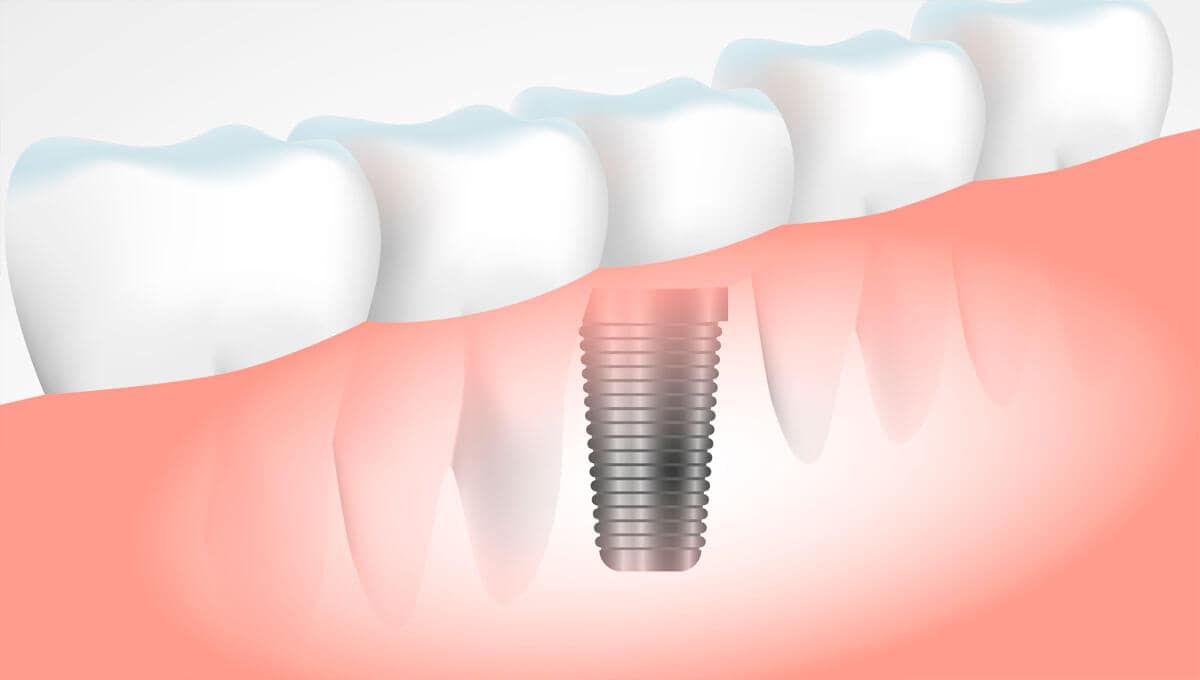

O implante dentário é a melhor forma de substituir um ou mais dentes perdidos. Nesta técnica, a raiz do dente perdido é substituída por um parafuso de titânio e neste parafuso é colocado a coroa, restaurando o dente perdido. Na Voito Odontologia você faz: